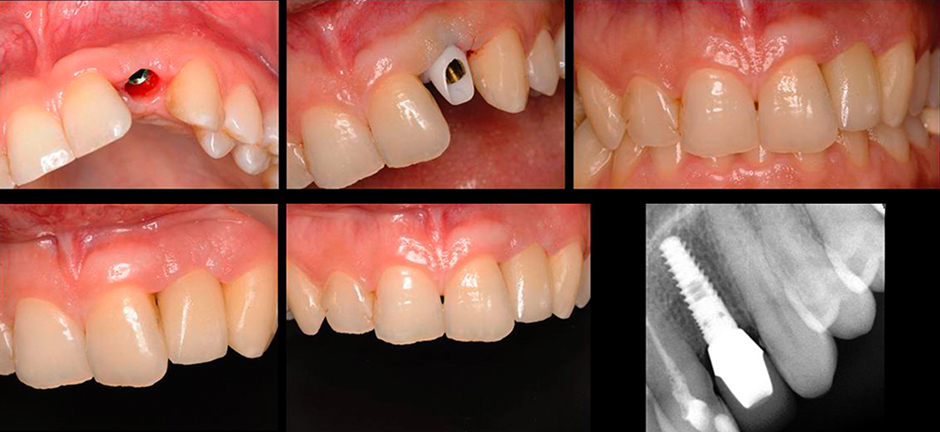

После закрытия винтового канала было выполнено сканирования абатмента с помощью inEos x5 и конструирование в InLab Software. После шлифования коронки из VITABLOCS Mark II, выполнена ее индивидуализация с помощью VITA VM 9 и VITA AKZENT Plus.